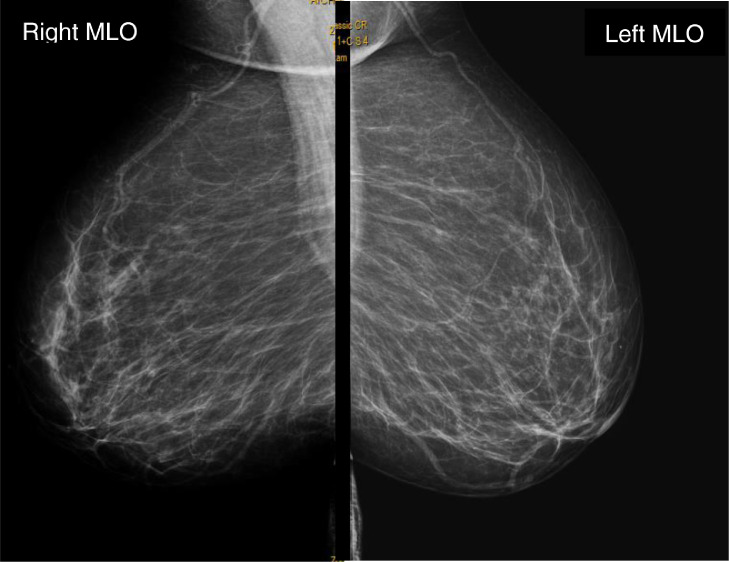

Mammogram and ultrasound of breasts were also performed and showed no notable abnormalities (Fig. 5).

Fig. 5.

Mammogram in mid-lateral-oblique incidence.